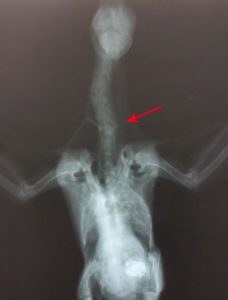

獸醫幫鴿姐照過X光,就估佢唔係揈甩頸,可能係飛飛下撞親,或者唔知邊個咁衰格當正阿鴿係揈頭鴿咁玩斷咗佢條頸囉,不過阿鴿啲手手腳腳都冇事,應該有得救嘅。人斷頸骨就話可以打石膏啫,鴿可以點搞呀?

首先要固定條頸先,用平日打石膏用嗰啲墊放喺頸度當頸箍再用綳帶包住,咁咪唔怕移位囉~本來醫生預阿鴿今次傷得咁重,應該有排先好得返㗎喇⋯⋯